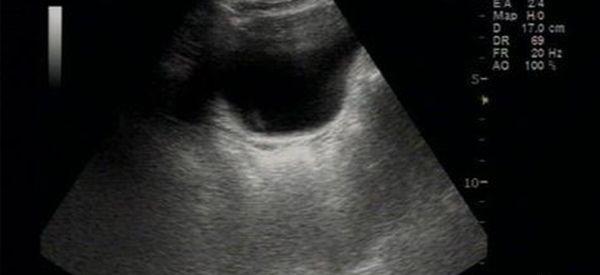

b超影像显示无子宫

先天性无子宫的诊断,一般是依靠B超检查来进行诊断的,通过B超检查,了解盆腔内是否有子宫的声像,如果在B超检查过程中发现盆腔内没有子宫回声,这种情况下就考虑为先天性无子宫,如果担心存在误诊的情况,也可以进一步考虑进行盆腔CT或者盆腔磁共振的检查。